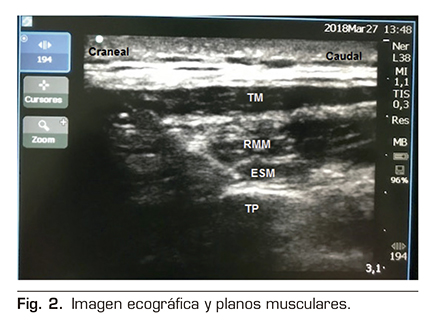

Se le realizó un bloqueo ecoguiado ESPB con colocación de catéter para analgesia continua posterior. Para ello, se colocó al paciente en posición de decúbito lateral derecho, y se procedió a la preparación de la zona de punción con povidona yodada, colocación de campo estéril y elección de sonda ecográfica lineal de alta frecuencia. Se identificó la apófisis espinosa de la 6.ª vértebra torácica y a una distancia de 3 cm lateral se identificó el proceso transverso de la misma. En la imagen ecográfica, visualizamos el plano subcutáneo y varios grupos musculares que de superficial a profundo corresponden con el músculo trapecio, romboides y erector de la columna, todos ellos sobre la apófisis transversa vertebral (Figura 2).